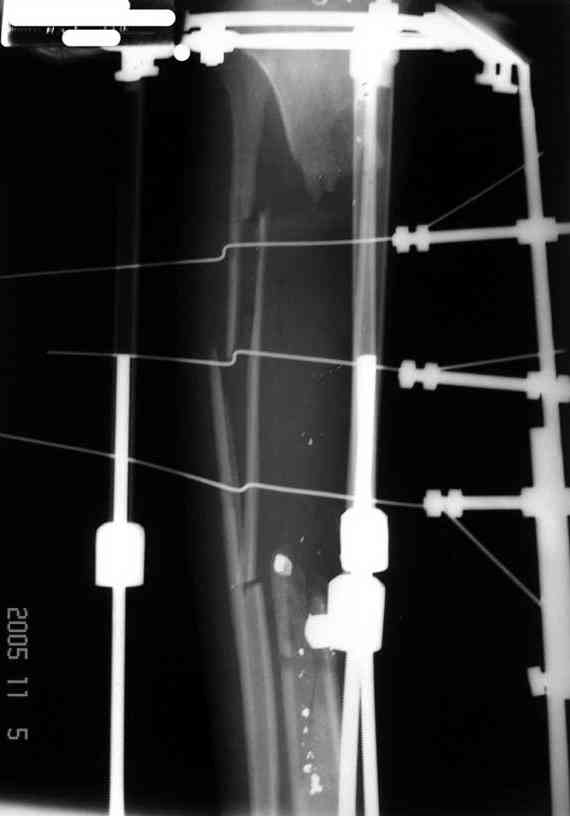

Отправлено Ласунский Сергей 30 Октябрь 2007, 23:53 РОСНИИТО им.Р.Р.Вредена

Пациентка с дефектом большеберцовой кости, возможно ли восстановление опороспособности нижней конечности? ДТП 1.5 года назад: открытый оскольчатый перелом средней трети левой голени с дефектом мягких тканей. Выполнены следующие операции в одной мз больниц города: 1.При поступлении ПХО и наложение АВФ 2.Нагноение резекция нежизнеспособной кости. 3.Пластика дефекта мягких тканей. 4.Попытка устранения дефекта по методу Илизарова, нагноение, радикальная хирургическая обработка, увеличение дефекта. 6 месяцев без признаков гнойного воспаления. В настоящее время иммбилизация гипсовой лонгетой до коленного сустава, функция коленного сустава сохранена, голеностопного нет.